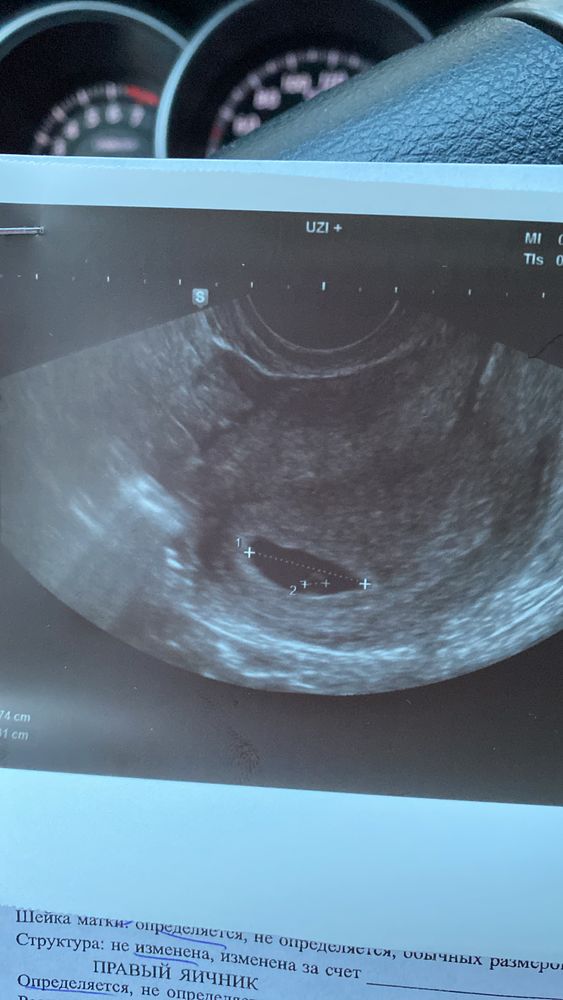

Цикл мой сегодня 90дц… я делала узи месяц назад и мне сказали что началась старая история снова МФЯ ановуляция и забеременеть мне будет сложно. Это сюр, потому что залёт случился в этот самый ановуляторный цикл 😂😂😂😂